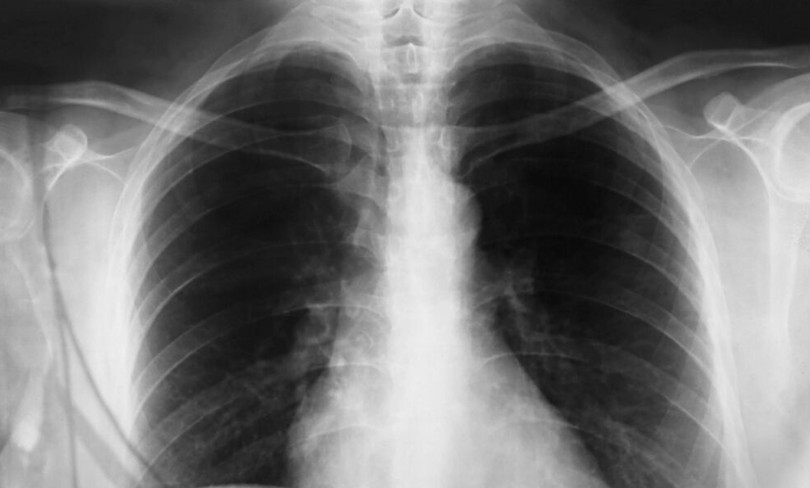

Ukoliko kašalj traje duže od tri nedelje, preporučuje se poseta pulmologu ili lekaru opšte prakse. Laboratorijske analize, uključujući testove na upalu, mogu pomoći u razlikovanju alergija od infekcija. Osim toga, alergijski testovi mogu identifikovati specifične alergene koji uzrokuju simptome. Kada se postavi tačna dijagnoza, važno je primeniti strategije koje će smanjiti izloženost alergenima, kao što su redovno čišćenje doma, korišćenje HEPA filtera i izbegavanje izlaska napolje tokom najintenzivnijih perioda za alergene. Osim dijagnostičkog testiranja, vođenje dnevnika simptoma može pomoći u identifikaciji obrazaca u vezi sa kašljem. Ako se utvrdi da je kašalj uzrokovan alergijama, lekar može preporučiti specijalne lekove koji pomažu u ublažavanju simptoma, kao što su antihistaminici ili kortikosteroidni sprejevi za nos. U težim slučajevima, imunoterapija može biti rešenje za trajno upravljanje simptomima. Ova metoda podrazumijeva postepeno izlaganje pacijenta alergenima u kontroliranim uslovima, što može vremenom smanjiti osjetljivost na te alergene.